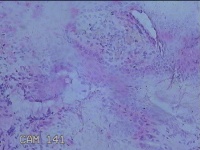

宫颈3点处组织

性别

女

年龄

35岁

临床诊断

宫颈上皮内肿瘤?

一般病史

月经干净4天,宫颈HPV亚型阳性,TCTASCUS。

标本名称

大体所见

灰白暗红色组织0.8x0.5x0.2cm一块。